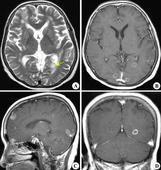

室管膜瘤(ependymoma)發(fā)生于腦室的室管膜細(xì)胞,占兒童中樞神經(jīng)系統(tǒng)原發(fā)性腫瘤5%~10%。好發(fā)于后顱窩,約60%。5歲以下兒童多見。瘤體多位于腦室內(nèi),少數(shù)在腦室旁組織內(nèi),呈緩慢、浸潤性生長。瘤細(xì)胞亦可脫落于蛛網(wǎng)膜下腔產(chǎn)生播散性種植。